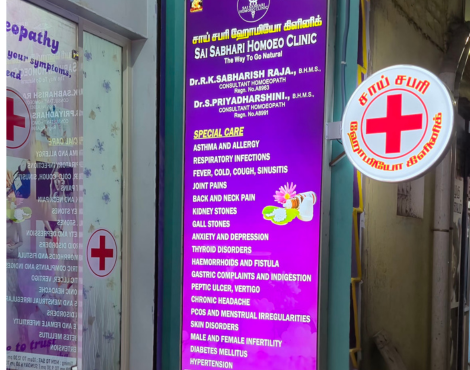

Dr. S. PriyadharshiniMon - Sat: 11 AM - 1 PM

Dr. R. K. Sabharish Raja

Mon - Sat: 6 PM - 9 PM

Sunday Closed

At Sai Sabhari Homoeo Clinic, we believe in treating the individual—not just the illness. With a focus on gentle, holistic care, our clinic offers personalized homeopathy grounded in trust and experience.